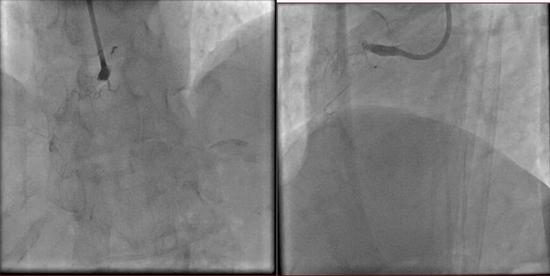

医院慢性全梗阻CTO介入手术 打通冠状动脉再

550x276 - 15KB - JPEG